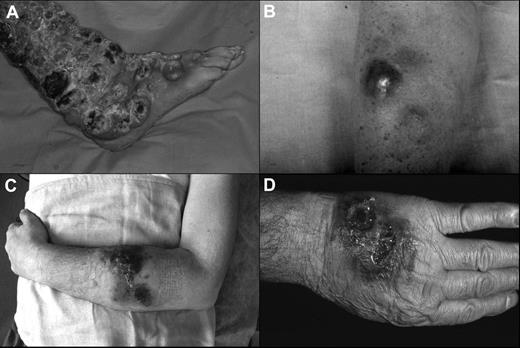

The clinical features of the patients are summarized in Tables 1 and 2. The median age was 60 years (range, 55-74 years) with a male-to-female ratio of 4:1. At the beginning, 4 patients showed exclusively cutaneous presentation (Figure 1A-C), whereas case 3 had both cutaneous (Figure 1D) and nasal-paranasal cavity involvement. The clinical presentation consisted of multiple nodules, confluent and diffused in 4 cases, and accompanied by ulceration in 2 cases. The distribution of the lesions was predominantly on the extremities (100%) and trunk (60%), especially the upper extremities (80%).

Clinical presentation of the patients. (A) Widespread ulcerated nodular lesions over the right leg (case 2); (B) erythematous-violaceous nodule on the arm at the onset (case 4); (C) plaques and nodules with ulceration and hemorrhagic aspects on the left arm (case 5); (D) nodular-ulcerative lesions localized on the left hand (case 3).